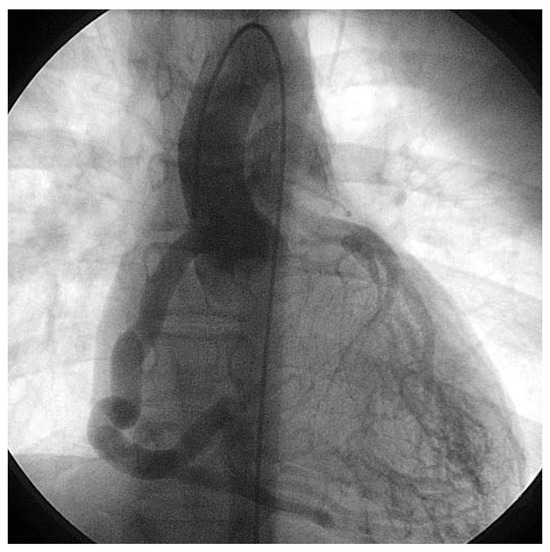

Very Late Stent Thrombosis of a Paclitaxel-Eluting Stent After Left Main Coronary Artery Stenting

by Stéphane Cook, Peter Wenaweser and Christian Seiler

Cardiovasc. Med. 2007, 10(5), 174; https://doi.org/10.4414/cvm.2007.01243 - 25 May 2007

Viewed by 171 Show Figures

Figure 1